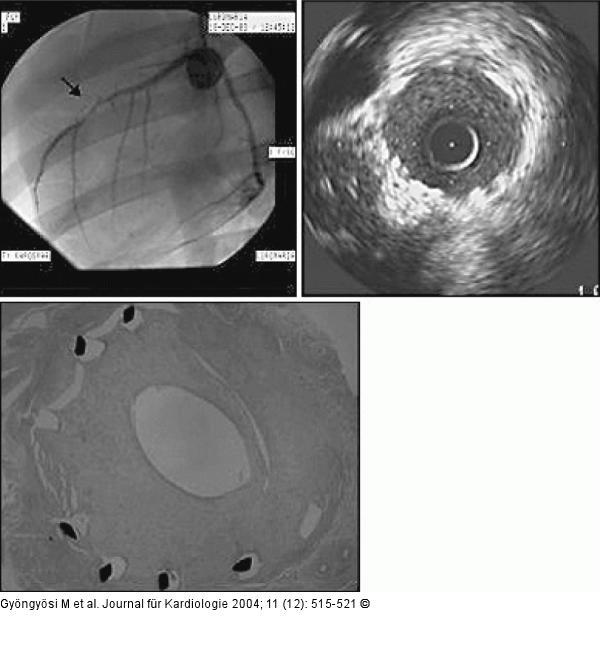

Abbildung 2: Arteria coronaria sinistra - Koronarangiographie Oben links: Koronarangiographie der linken Koronararterien → Hochgradige In-Stent- Stenose in der LAD mit distal reduziertem Fluß. Oben rechts: Querschnitt des Koronargefäßes, dargestellt mit intravaskulärem Ultraschall und (unten) Histologie. Dicke neointimale Hyperplasie 1 Monat nach Stentimplantation. |